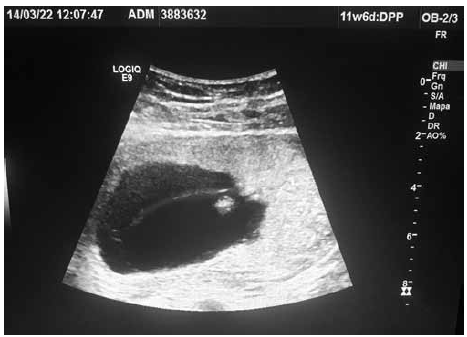

Paciente com IG de 12 semanas pela DUM veio à medicina fetal para realização de seu primeiro ultrassom obstétrico. Identificadas as figuras 1 e 2 (em ângulos e posições diferentes), conforme ilustrado.

Com base nas imagens em conjunto, assinale o diagnóstico correto é: